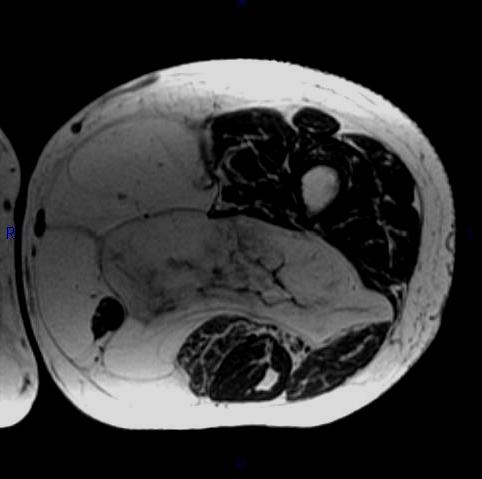

MRI (Fig. 1, 2, 3 and 4)

• Large encapsulated lipomatous mass. (Fig. 1, 2, 3 and 4)

• Greater than 75% adipose tissue (Hyperintense on T1-weighted) (Fig. 1)

Fig. 2-4 MRI: Coronal T2-weighted fat suppressed (Fig. 2) and Axial T2-weighted FS (Fig. 3) shows low intensity signal isointense with fat. Adypocitic lesion with fatty signal is located in the posterior and medial compartment of the thigh. Thickened septa and nodularity enhances on post contrast images. (Fig. 4)